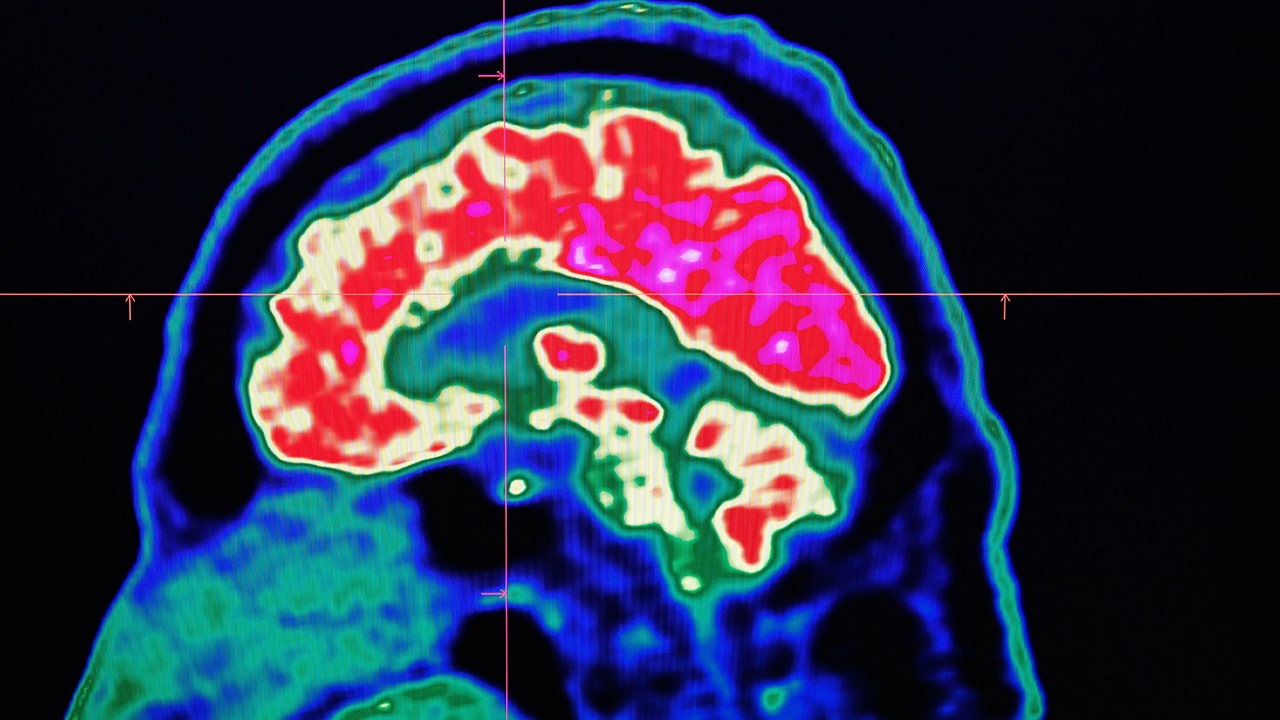

Brain fog is one of the biggest symptoms in those with long-haul COVID-19. Researchers are working to combat the issue and to find out what causes it.